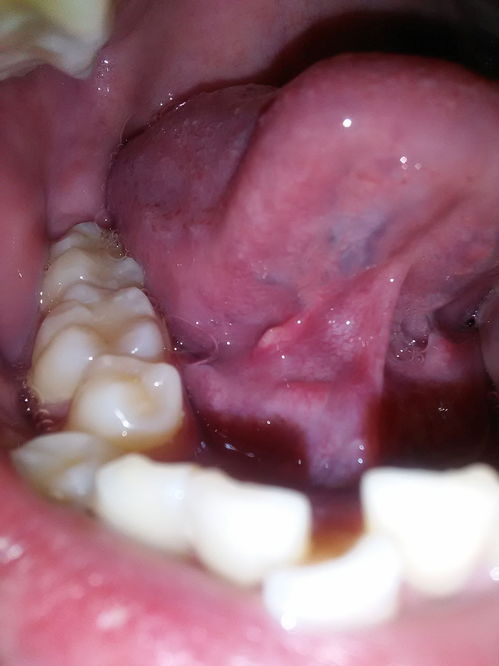

孩子舌系帶不要盲目割 舌系帶長(zhǎng)短要經(jīng)醫(yī)生確診 所謂舌系帶,就是人們俗稱(chēng)的舌筋。

舌下的黏膜薄而平,反折時(shí)與舌下區(qū)的黏膜相延續(xù),此時(shí)在舌背側(cè)中間有一條筋膜連接舌與舌下黏膜,這條筋膜就是舌系帶。舌系帶過(guò)短會(huì)影響發(fā)音,常表現(xiàn)為舌不能自由前伸,舌頭伸出后不能碰到上唇,舌頭在口內(nèi)不能頂?shù)缴想?,舌頭伸出后呈M型或者舌頭伸出后有小溝。